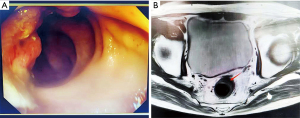

Preoperative preparations and requirements

We selected a patient with rectal cancer who was treated at the Fourth Hospital of Hebei Medical University. The patient was a 75-year-old male admitted in March 2023 due to hematochezia lasting for more than 1 month which was accompanied by increased defecation frequency, anal tenesmus, and other discomfort, but no abdominal pain or bloating. His body mass index (BMI) was 20.1 kg/m2, and his Eastern Cooperative Oncology Group Performance Status score was 0. He had a history of hypertension, anxiety disorder, and prostatitis for more than 10 years. Rectal digital examination (in the knee-chest position) indicated a normal anal appearance. A finger was inserted about 7 cm into the anus, and no bloodstain was found on the finger cot after withdrawal. Chest and abdominal computed tomography (CT) showed thickening of the rectal wall, consistent with intestinal cancer, no metastases to other organs were observed. Colonoscopy revealed an ulcerative neoplasm at about 10 cm from the anal margin, involving half of the intestinal lumen, while the rest of intestine appeared normal (Figure 1A). Pelvic high-resolution magnetic resonance imaging (MRI) suggested a rectal wall mass consistent with rectal cancer (imaging stage T2N0M0) (Figure 1B). The pathological diagnosis was adenocarcinoma. According to the Chinese Guidelines for the Diagnosis and Treatment of Colorectal Cancer (8), for middle rectal cancer (cT2N0M0) with a small tumor in a patient with a normal BMI, fluorescence navigation–assisted radical resection is recommended for precise diagnosis and treatment. Thorough preoperative preparations were completed in our ward, including a comprehensive assessment of the patient’s physical condition, appropriate bowel cleansing, nutritional support, psychological counseling, and other treatments. All procedures performed in this study complied with the ethical standards of the relevant institutional and/or national research committees and adhered to the Declaration of Helsinki and its subsequent amendments. Written informed consent was obtained from the patient for the publication of this manuscript, accompanying images, and the video. A copy of the written consent is available for review by the editorial office of this journal.